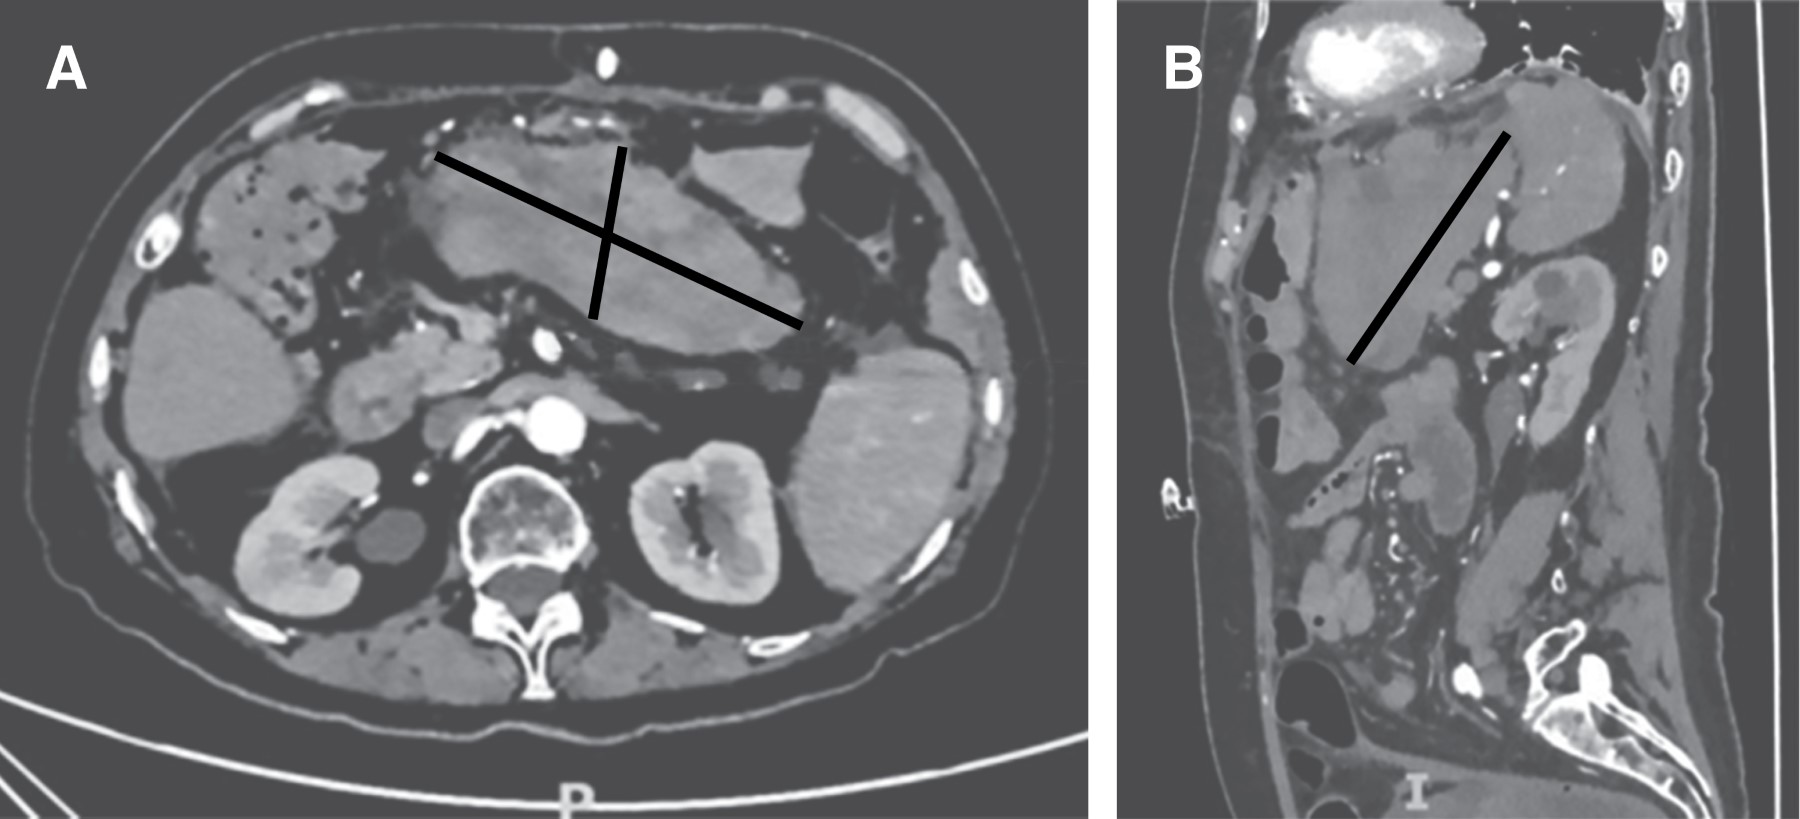

Dos semanas posteriores, la paciente ingresa a hospitalización por síntomas respiratorios y disminución de hemoglobina, por lo que se toma una TAC de control evidenciando un hematoma epigástrico de 11.8 × 5.5 × 10.8 cm sin datos de sangrado activo (Figura 2). Se transfunden dos paquetes globulares, logrando estabilidad hemodinámica y posterior alta de hospitalización.

Figura 2